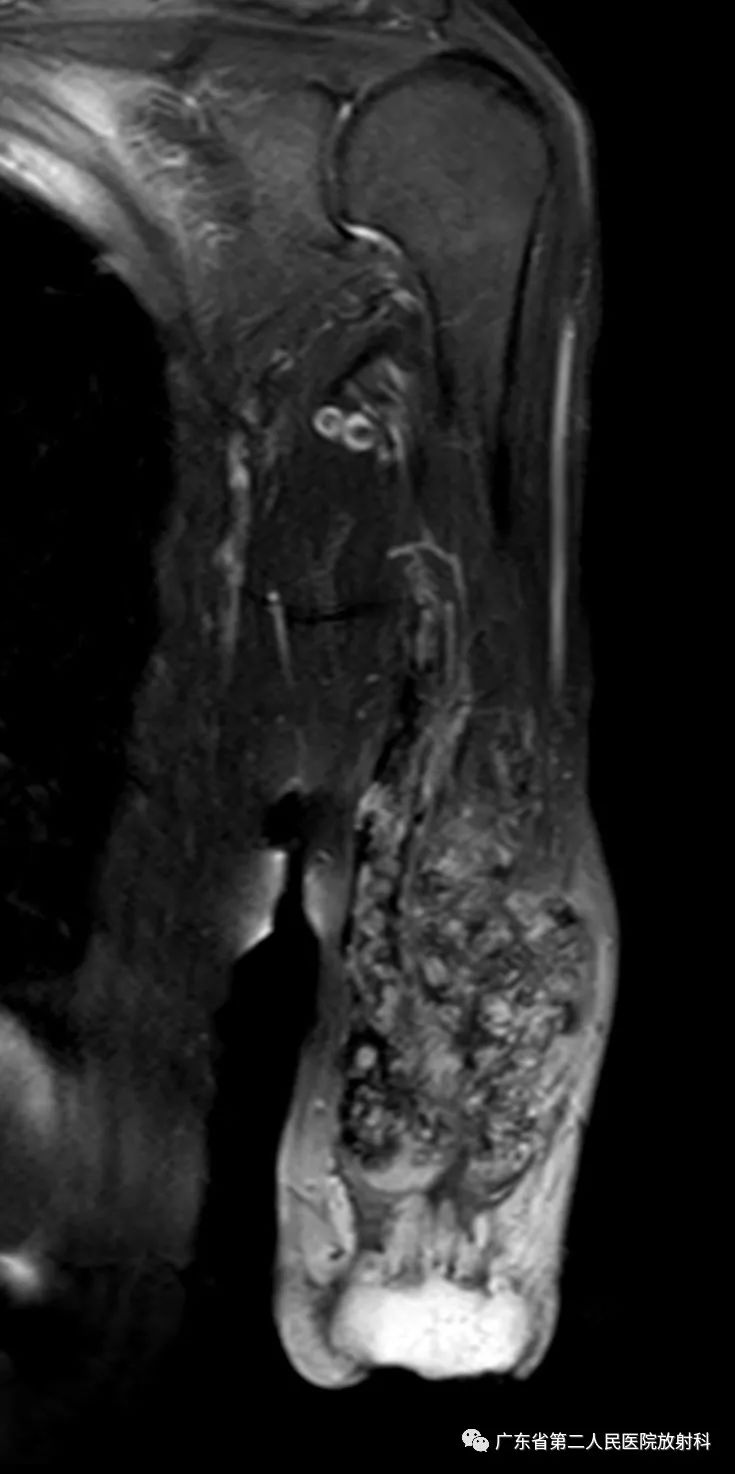

T1增强

左上肢前壁截肢术后观,左上臂中下段见团块状异常信号,病灶信号明显不均,整体以长T1长T2信号影为主,增强扫描呈明显不均匀强化,末端球形膨大,内见散在少许团絮状短T2长T1且无强化信号。冠状位示病灶整体呈梭形改变,边界欠清,部分包绕肱骨下段,以长T1长T2信号为主,散在少许短T2信号,增强扫描明显不均匀强化,内见散在少许团絮状短T2长T1且无强化信号。肱骨下端边缘欠光整,骨髓未见明确异常信号。